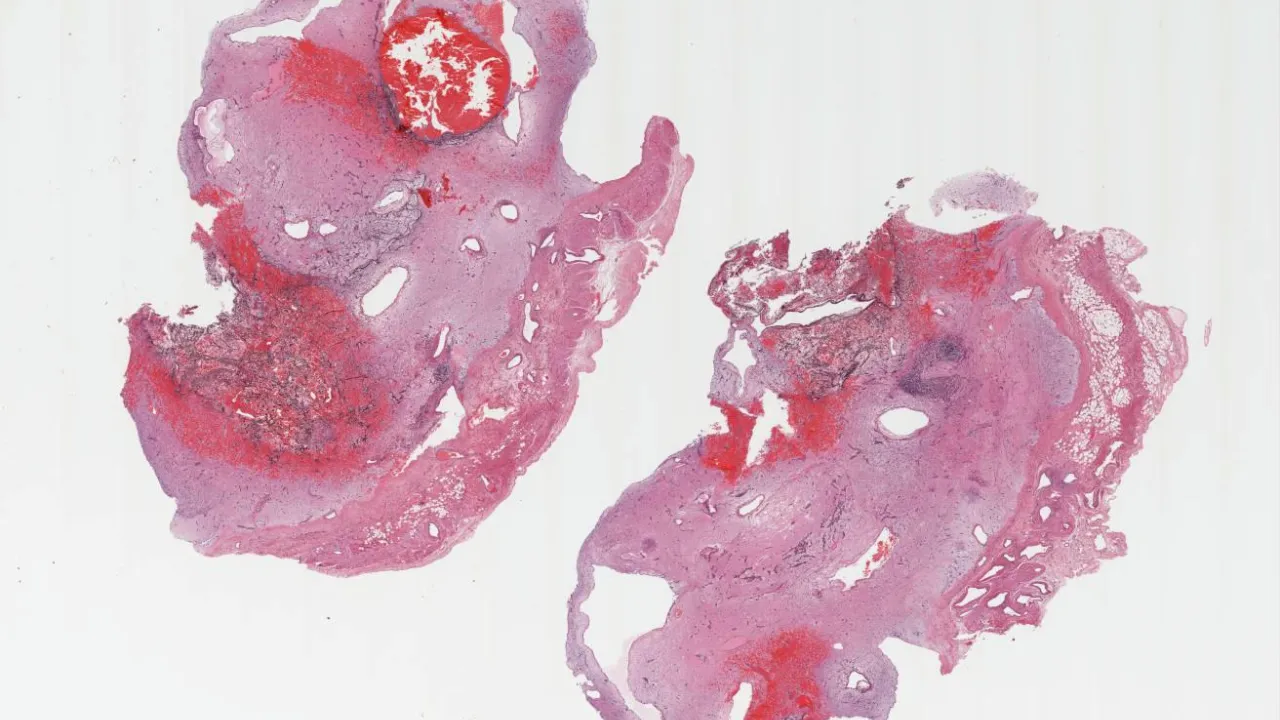

Heart, Cardiac myxoma